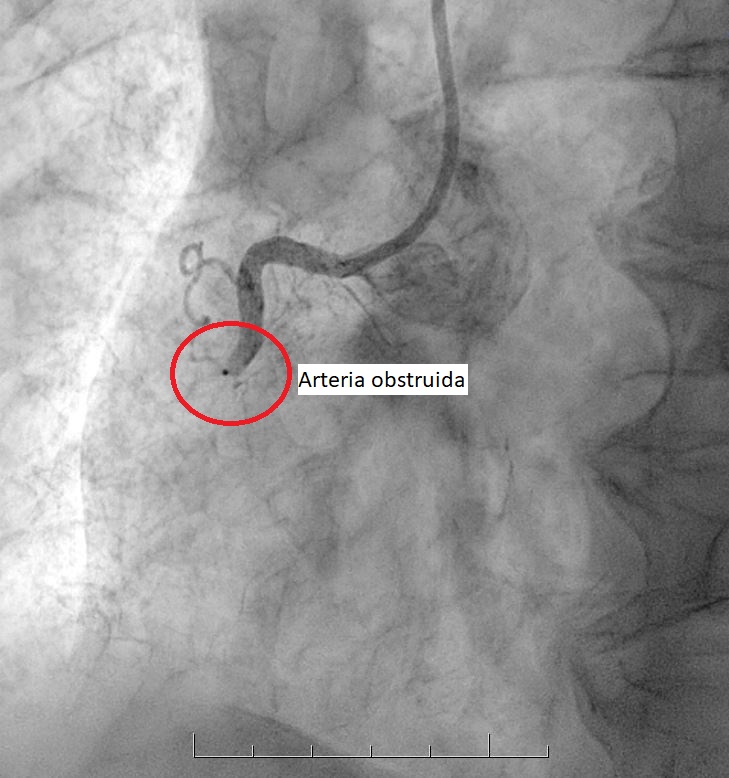

• Es un procedimiento que permite eliminar las obstrucciones de las arterias, abriendo el paso a la circulación de la sangre y dejando lugar para la colocación de un stent.

• La enfermedad coronaria se produce por la obstrucción de las arterias que llevan sangre al corazón. Para tratarla, existen tres métodos básicos: medicamentos, angioplastía o cirugía cardiovascular (by-pass).

Este catéter llega hasta las arterias que se van a tratar y una vez allí se inyecta una sustancia de contraste, que permite visualizar las obstrucciones existentes. A través de este catéter se inserta un balón, que se expande en el sitio obstruido y luego se retira, dejando lugar para la colocación de un stent.